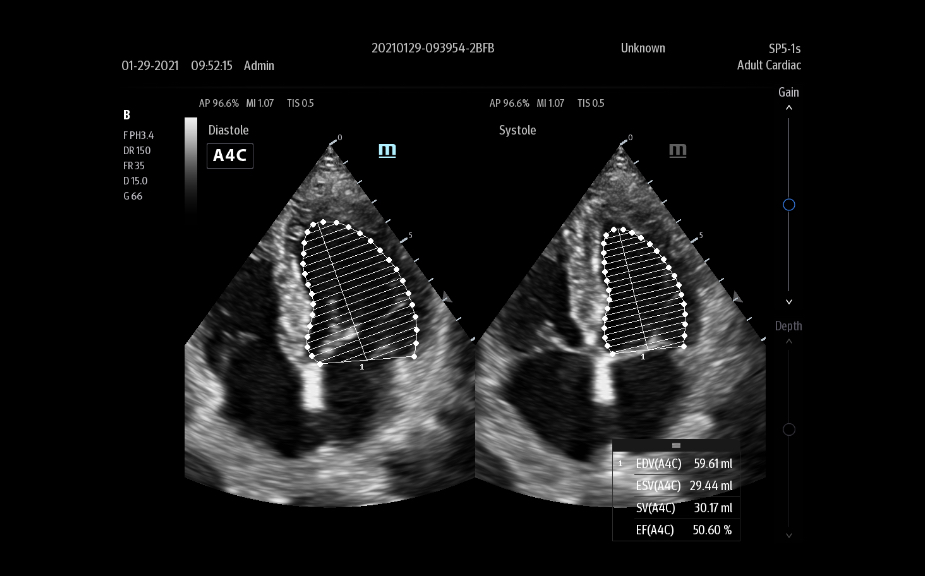

Images